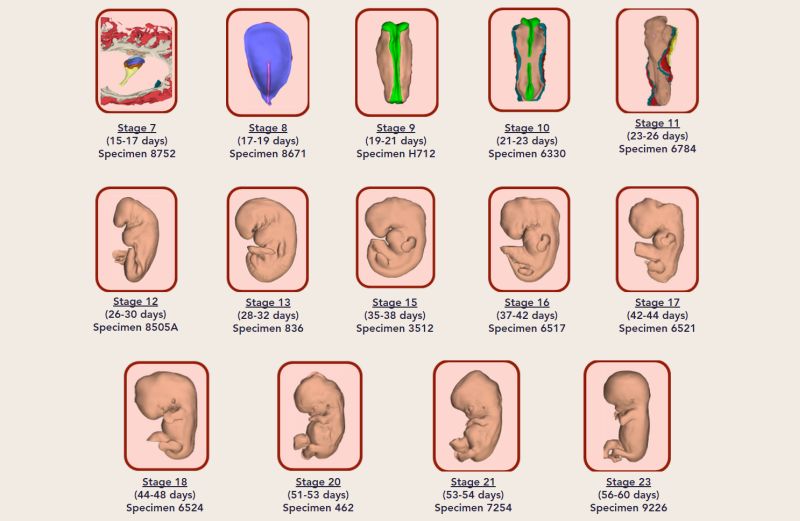

Нидерландские ученые создали трехмерный атлас пренатального развития человека в первые два месяца после зачатия. Об этом сообщает 3D Embryology.

Ученые Академического медицинского центра в Амстердаме идентифицировали и промаркировала 150 структур и органов тела эмбрионов, после чего реконструировали их трехмерные компьютерные модели.

Результаты исследований сгруппировали в единый атлас развития эмбриона в период от 15-17 до 56-60 дня после зачатия.

Все модели были классифицированы по стадиям развития и превращены в интерактивный формат 3D-PDF, который находится в свободном доступе.

Атлас позволяет рассмотреть как эмбрион в целом, так и его отдельные структуры, органы и системы.

Для более полного понимания ученые указали размеры эмбриона в миллиметрах и по сравнению с ладонью взрослого человека.